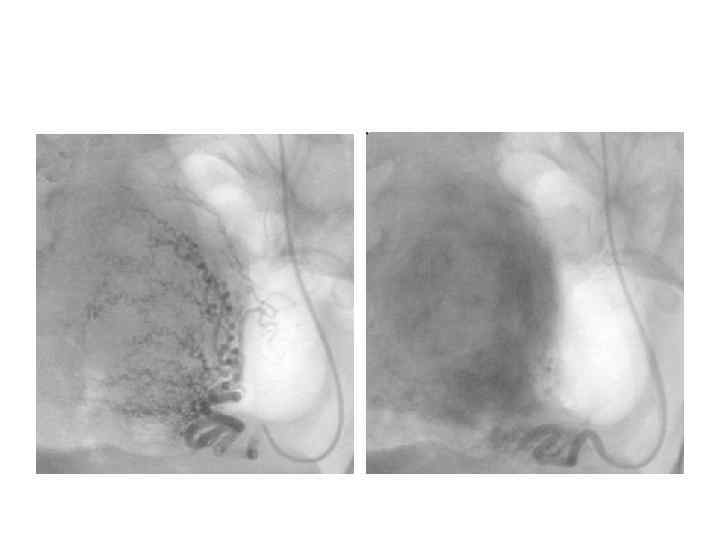

Метод Дьюка а) у здорового человека (время кровотечения 3, 5 мин. ) б) у больного с выраженной тромбоцитопенией (время кровотечения 20 мин. )

Запомните! • В норме время кровотечения по Дьюку не превышает 4 мин. Его увеличение наблюдается при выраженных тромбоцитопениях или/и тяжелых нарушениях их функции (тромбоцитопатиях). • Следует помнить также, что у 60 % больных с этой патологией тест оказывается отрицательным, и время кровотечения нормально.